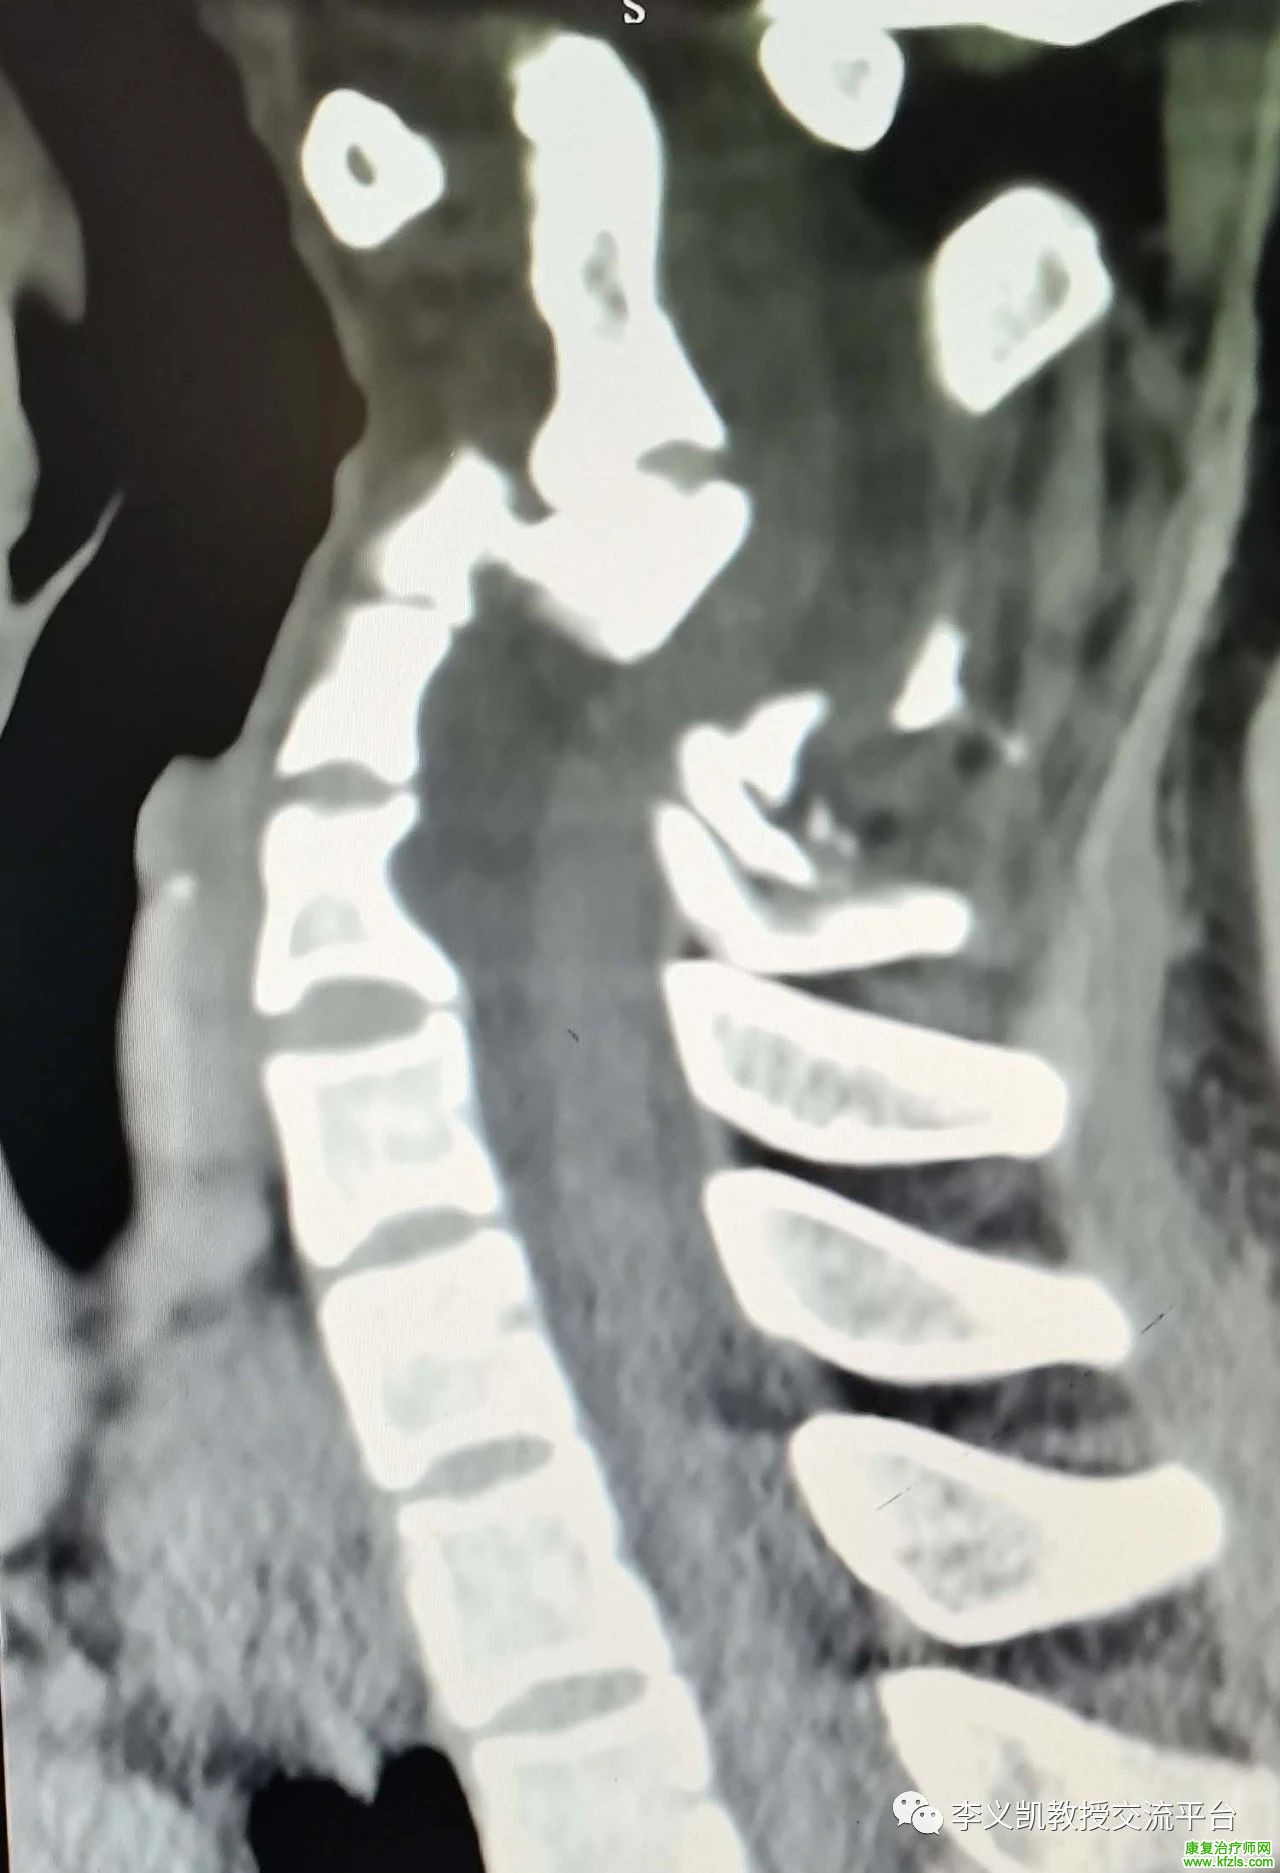

作为一名专业的物理治疗师,平时会遇到很多颈肩腰腿疼的患者,手法治疗成为最常用的方式之一,但是平时一定要谨慎下手,转载自李义凯教授的交流平台的文章,本病例很常见,有警示作用,值得认真阅读下,这是一例C3骨折脱位向后移位明显的病例。

本例患者的颈椎矢状位CT片可见,其C3骨折脱位向后移位明显,占据椎管空间,患者右侧霍夫曼阳性,左侧阴性,颈活动度稍差。患者的病情十分危险,建议及早手术复位内固定,解除对脊髓的压迫,以免压迫时间过久伤及脊髓,造成难以恢复的损害。图1中最左侧的箭头是寰椎的前结节,中间的箭头为齿状突,右边的箭头为寰椎的后结节。